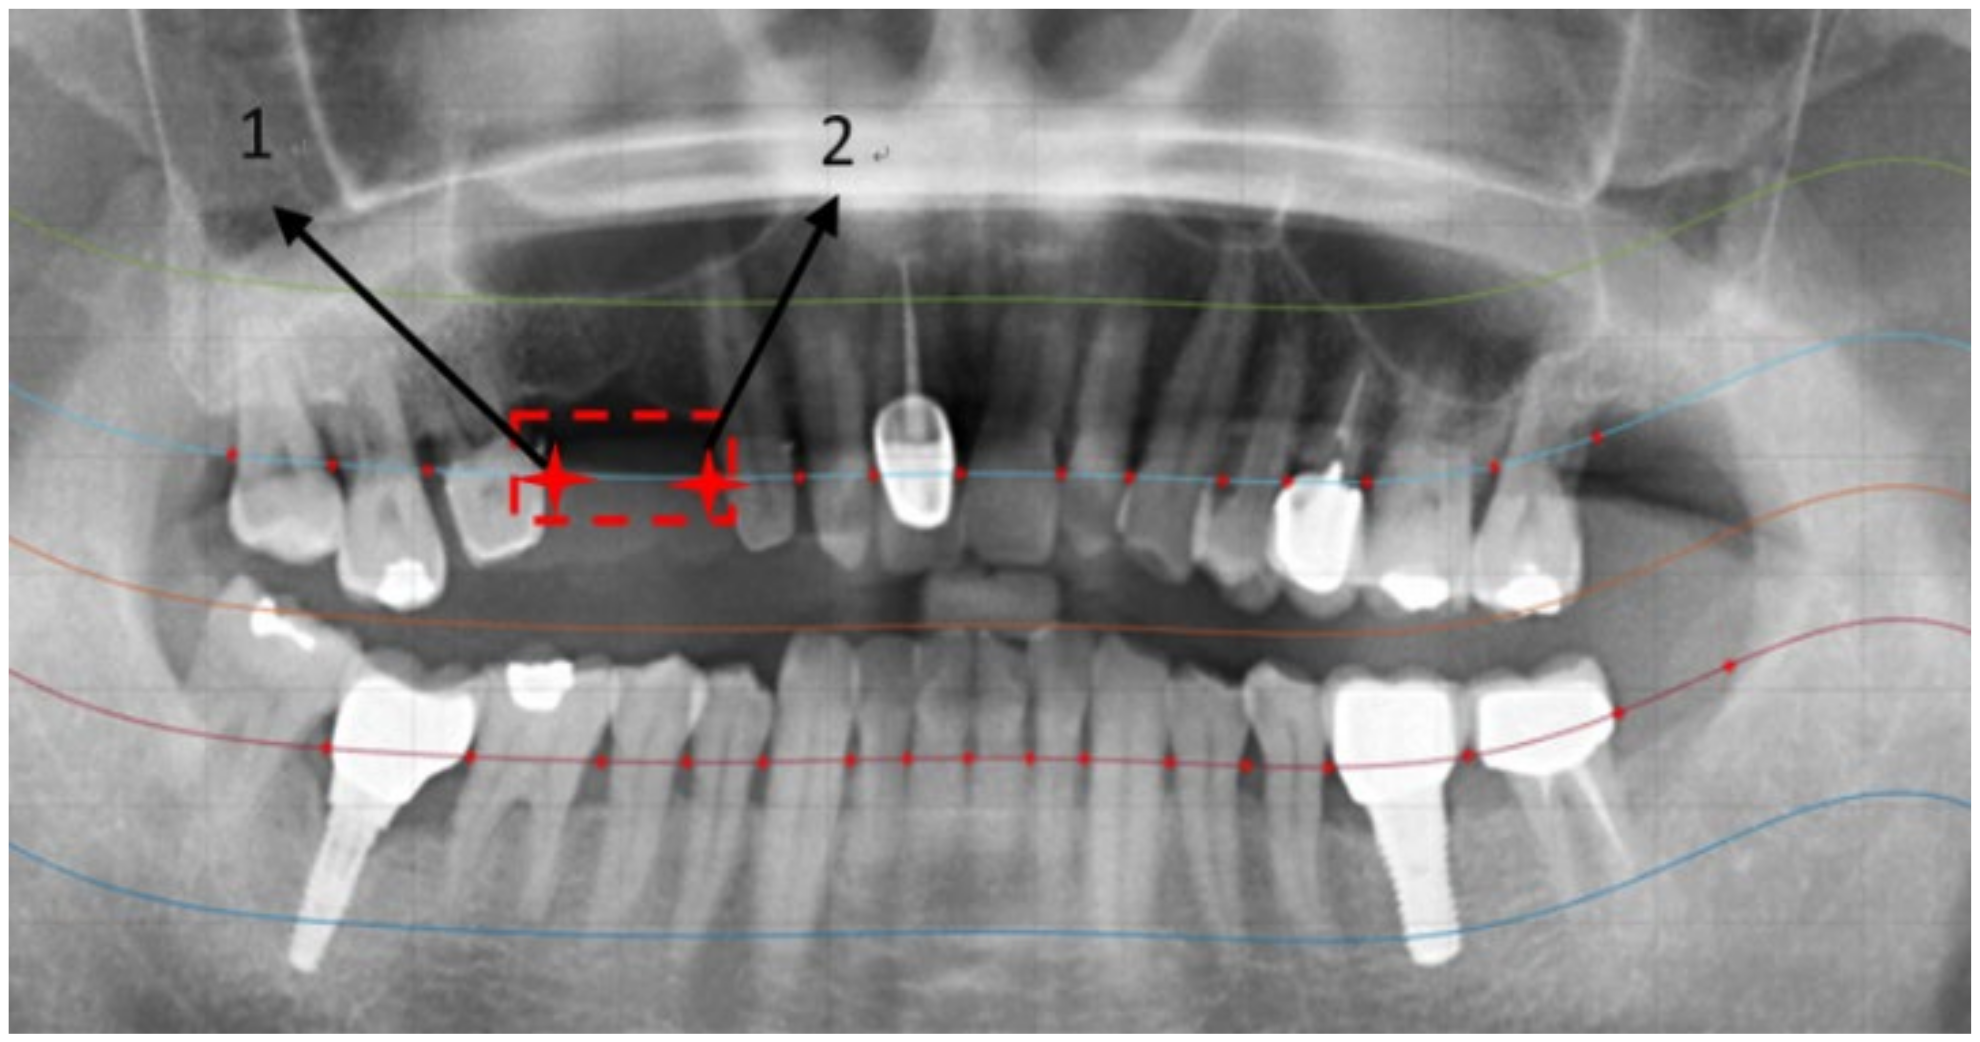

2.2.3. Positioning Numbers

3. Results

| Tooth Position | [14] | Our Method |

|---|---|---|

| 18 | True | True |

| 17 | True | True |

| 16 | True | True |

| 15 | False | True |

| 14 | False | True |

| 13 | True | True |

| 12 | True | True |

| 11 | True | True |

| Positioning Accuracy Rate | ||

| Method in [26] | Our Method | |

| Positioning accuracy rate | 71.36% | 92.78% |